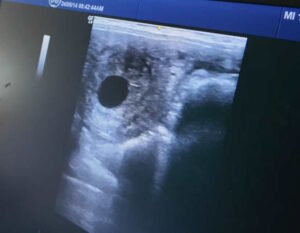

コラム・エッセイ ブログ・手記 [連載・片目のサラブレッド福ちゃんのPERFECT DAYS]僕たちが手がけているのは命のある生き物(シーズン1-37) 2025年3月11日 川崎競馬のパドック解説を終え、入場門の外に出ると、僕は真っ先に慈さんに電話をかけました。もう遅い時間だから寝ているかもと心配しましたが、慈さんは日高の生産者たちとの飲み会がちょうど終わったところだったようで、あっさりと電話に出てくれました。 「スパツィアーレの23のレポジトリの結果が今日出ましたので」と慈さんが切り出し... 治郎丸敬之